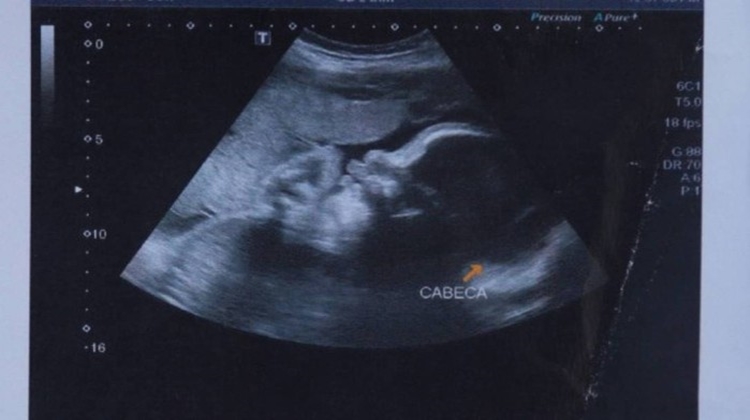

A mãe de Arthur, Claudineia dos Santos Melo, foi baleada no dia 30 de junho, na Favela do Lixão. O bebê, ainda no útero, também foi atingido. Claudineia foi levada para o Hospital Moacyr do Carmo, onde médicos realizaram uma cesárea de emergência.

O menino foi transferido, depois, para o Hospital Estadual Adão Pereira Nunes, onde estava internado desde então. Dois dias após Arthur ter sido baleado, um laudo médico apontou que ele corria o risco de ficar paraplégico.